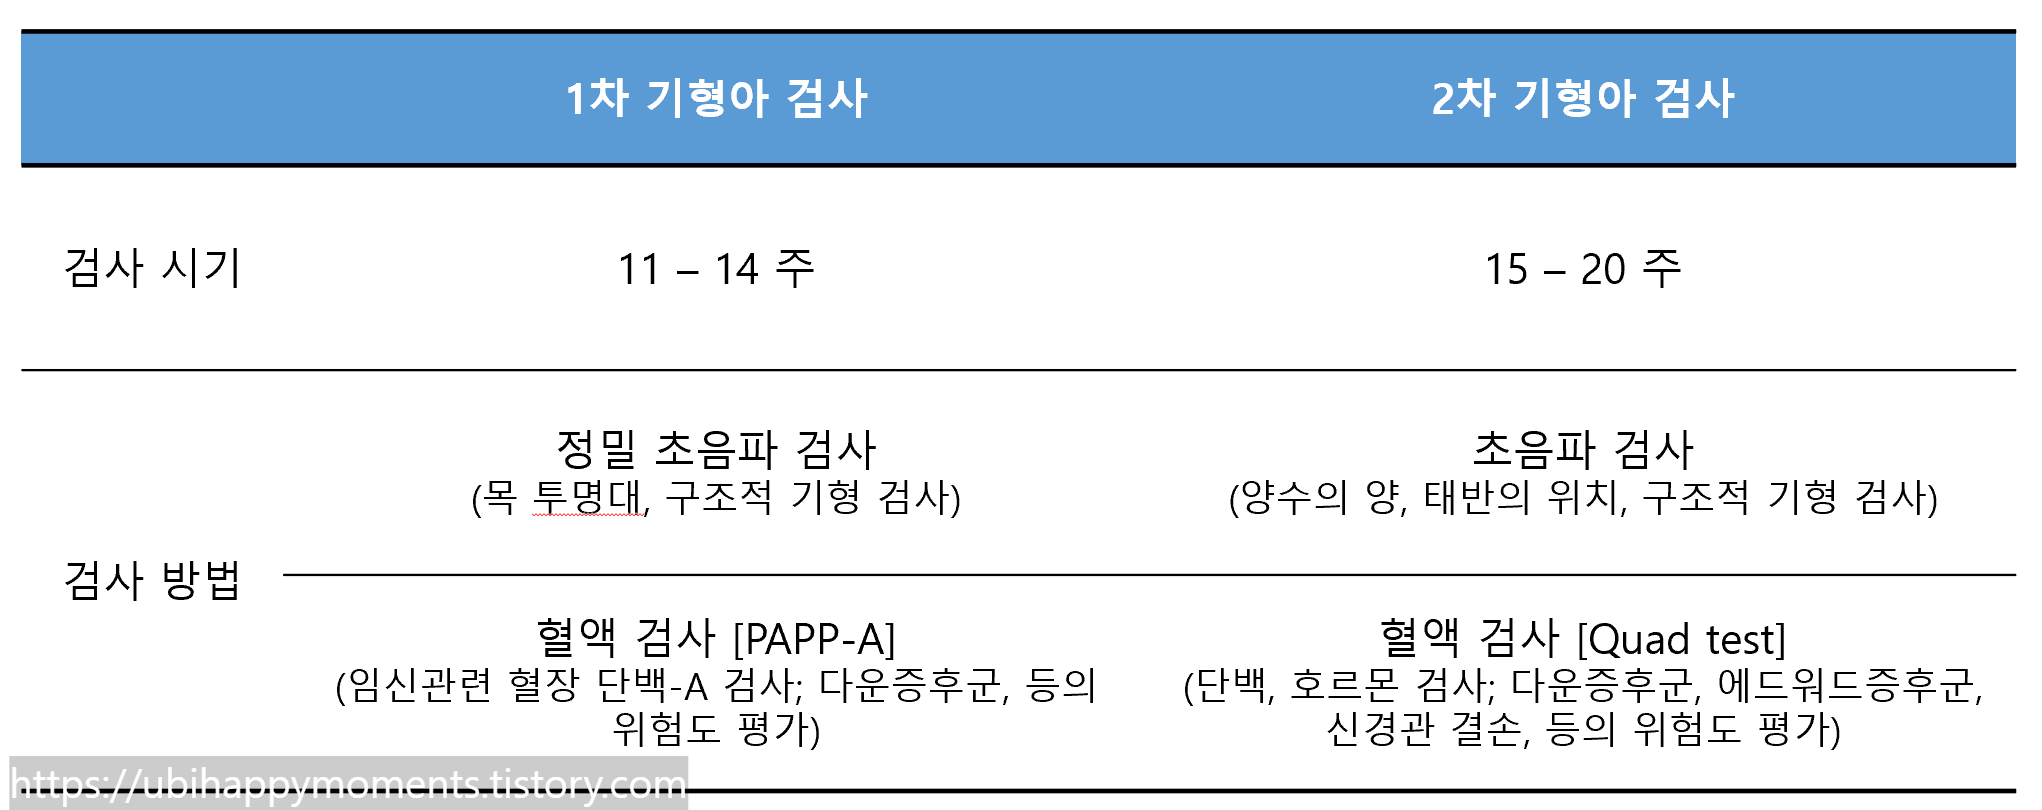

1차 기형아 검사와 2차 기형아 검사의 차이

1차 기형아 검사와 2차 기혐아 검사는

초음파 검사 외에도

혈액검사를 진행합니다.

1차 기형아 혈액검사는 PAPP-A 검사로 임신 초기에 시행해서 조기 선별이 가능하고

2차 기형아 혈액검사는 Quad test로 임신 중기에 시행하여 보다 다양한 기형 평가가 가능합니다.

최종적으로 전반적인 기형아 검사의 저위험군인지? 고위험군인지? 가 결정되는 방식입니다!

그래서 1, 2차 기형아 검사가 모두 이루어져야 최종 결과를 확인할 수 있다는 점!